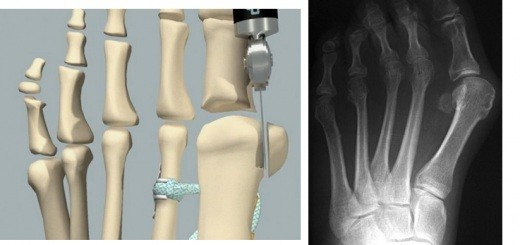

强生子公司DePuy Synthes 推出了TRUMATCH产品线,产品包括定制化的颅颌面(CMF)外科植入物和手术导板,以及膝关节手术导板。

图片来源:DePuy Synthes

DePuy Synthes 的临床工程师根据病人的CT 扫描数据创建定制化CMF植入物和手术导板。在CMF 领域DePuy Synthes 一个重要的合作伙伴是Materialise 公司,Materialise为DePuy Synthes制造个性化CMF手术导板,并将为DePuy Synthes 供应定制化的颅颌面植入物。这些植入物将通过TRUMATCH CMF Solutions公司在澳大利亚和欧洲(不包括法国)出售。

此外,DePuy Synthes的临床工程师通过Materialise公司的ProPlan CMF规划软件在一个虚拟环境中配合医生制订手术前计划、定义植入物的形状、并设计手术导板,然后生成可3D打印的输出文件。

膝关节手术导板也同样是根据患者膝关节部位的CT 数据进行创建。这些器械的创建、制造过程是在DePuy Synthes于3D Systems公司合作下完成的,两家公司已建立了长期合作关系。所有的外科导板设计、与外科医生的沟通和整个产品生命周期管理,是由一个专门的小组来负责。植入物等医疗器械的设计文件经过外科医生批准后,会被传送给3D Systems公司进行打印,然后送回到DePuy Synthes进行最后的组装、杀菌和装运。

定制化设计的植入物能够与病人的解剖结构相匹配,从而减少并发症的发生,手术导板在手术过程中帮助指导医生切骨和准确定位植入物,从而减少手术过程中的不确定性,并减少手术时间。这些定制化的植入物复杂的几何形状往往只有3D打印技术才能够实现。